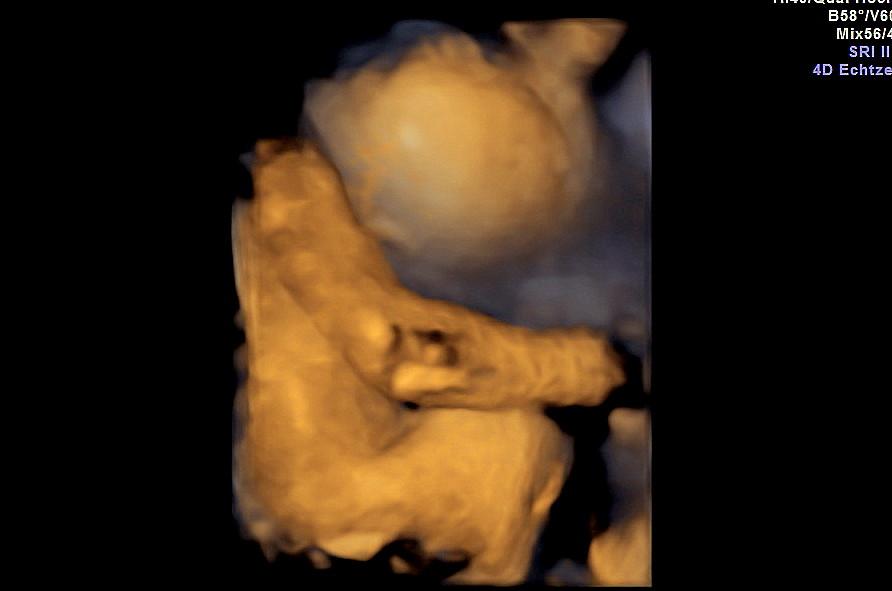

Moc gratuluji.Tak to už jsou kočičky veliké.-)Také čekám dvojčátka,tak doufám,že všechno dobře dopadne.Vzpomeneš si,v jakém týdnu si věděla pohlaví?Měla jsi nějaké problémy s dvojčátky?Mě samozřejmě před transferem varovali,že děloha je na jedno mimčo,aby se pak neutiskovali,předčasný porod,ale říkala jsem si,že problémy můžou být i s jedním a že si vezmu oba poslední mrazáčky

@martinaanet ja mela strasne moc vajicek, odebrali jich 43 a 15 jich je na mrazaku, 2 tam daly hned za cerstva na moje prani, netusila jsem, ze se chytnou obe, myslela jsem, ze je to jen takova jistota protoze ja byla na IVF uz pred 12 lety a dvojcata jsem mela jen do 9 tydne, pak se jedno vstrebalo a tak mam 12 letyho rostaka. povedlo no, jsme radi 🙂 pohlavi mi rekla doktorka v 18 tydnu. Ve 21 to jeste jednou potvrdila. co se tyce problemu, zadne extra nemam, neotekam, tehotenskou cukrovku nemam, ale vody mam hodne a mam velke problemy s dychanim, je to teda zahul jako prase, nebudu rikat, ze ne 🙂

Děkuji.Já jsem si dala 2x1,pak 2 a stále nic a zbývaly 2 mrazáčky,tak jsem si je dala oba a vyšlo to,i když samozřejmě vím,že se ještě může stát cokoliv.8.12.se dozvíme,jestli jsou děti zdravé,z toho už jsem docela nervozní.to čekání je dlouhé.Aty problémy s dýcháním máš až ted poslední dobou nebo už déle?Věděla jsem předem,že je to se 2 komplikovanější,ale přesto jsem do toho šla,i když jsem přesně nevěděla,co to může obníšet.Vám už to uteče a na jaře budete drandit a já se budu asi valit🙂